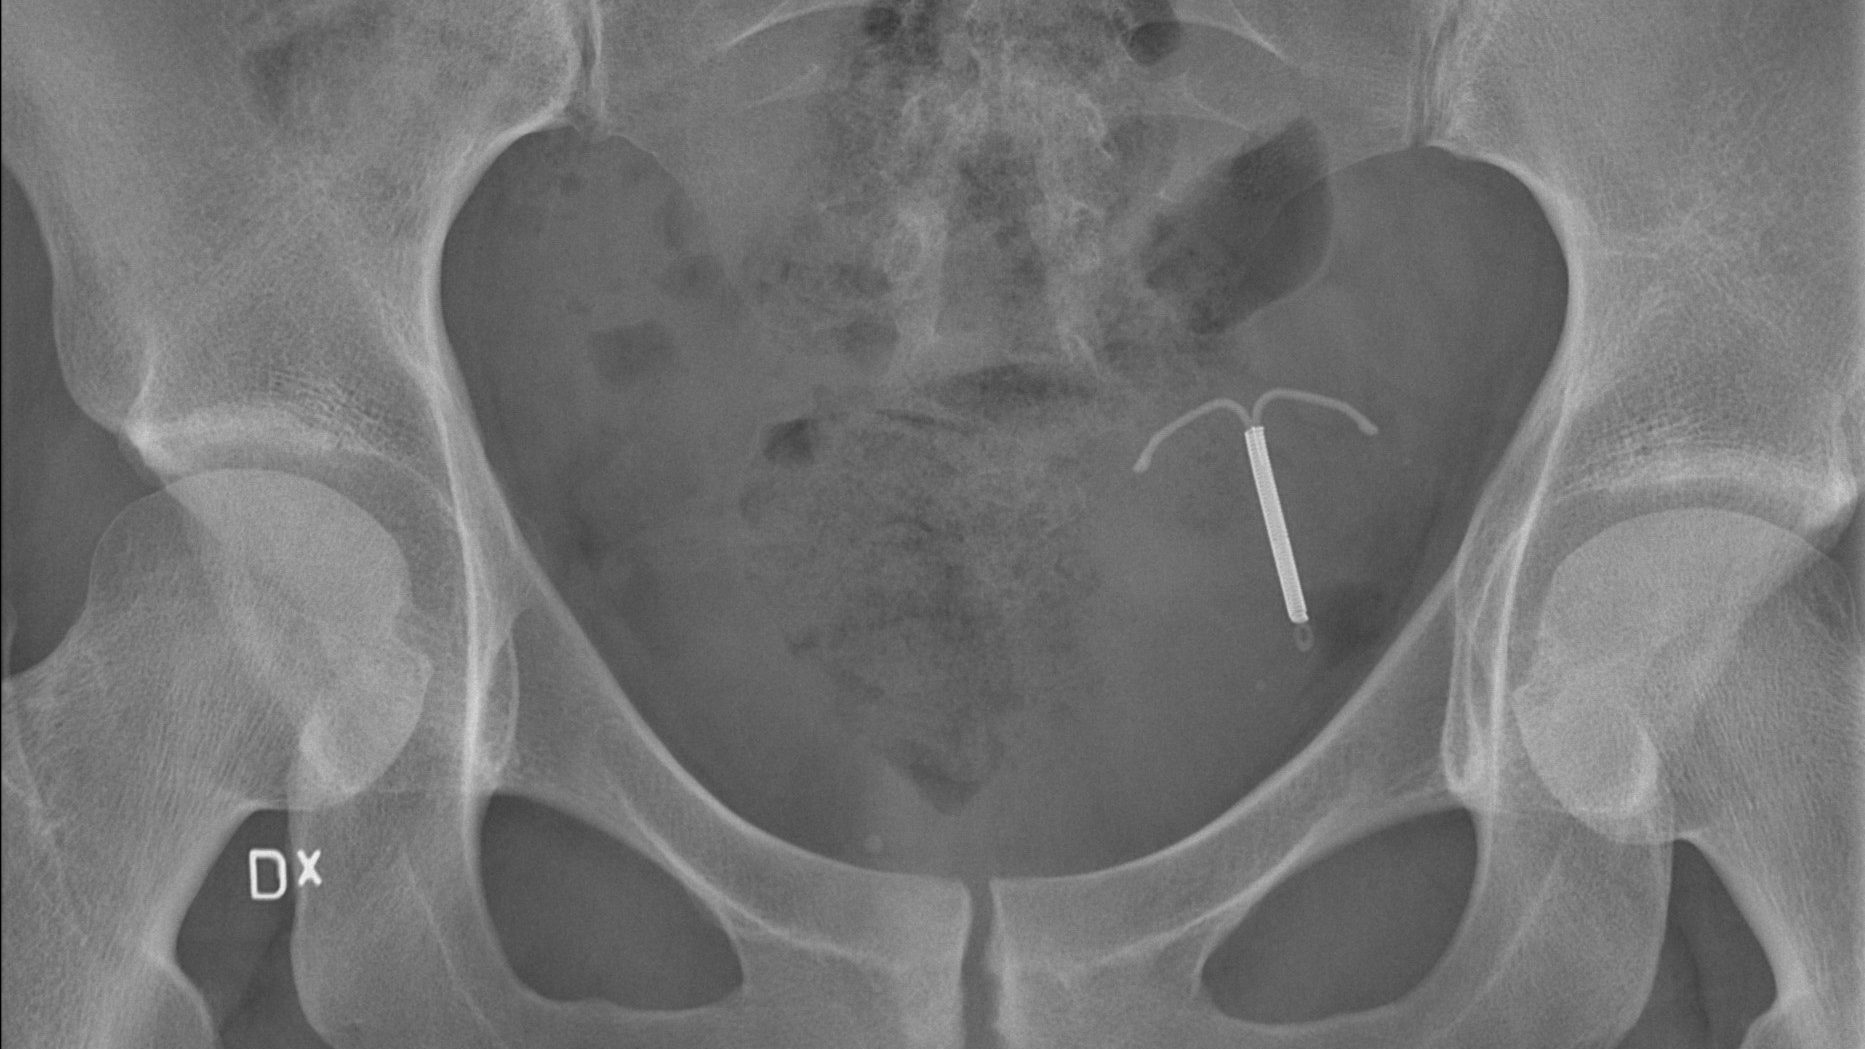

I essän beskriver hon en annan sida av myntet, inte minst den motsägelsefulla bristen på frihet, att inte riktigt kunna välja själv utan att pressas till ett beslut. Hon beskriver ett tryck på kvinnor, och inte minst unga kvinnor, att använda hormonella preventivmedel hellre än till exempel kondom, eftersom det ofta anses vara det bästa alternativet, även när man tagit negativa biverkningar i beaktande. Biverkningar som kan inkludera allt från fysiska förändringar som akne, viktuppgång och ökad kroppsbehåring, till personlighetsförändringar: ett depressivt humör, nedsatt sexlust, ångestattacker. Trots väldokumenterade, vanliga biverkningar fortsätter hormononella preparat för kvinnor att vara en av de vanligaste formerna av preventivmedel. Liknande preventivmedel för män saknas dock helt, eftersom marknaden tydligen inte anses kunna ta emot en sådan produkt.